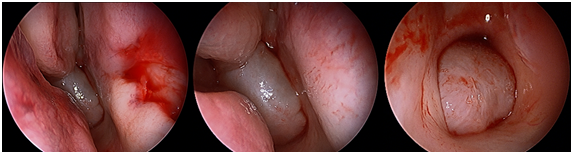

A 27year old female presented in OPD with complaint of right side nasal obstruction since two years with mouth breathing and snoring since 1year. Symptoms were gradually progressive. There were no allergic symptoms like rhinorrhea or recurrent sneezing. Her anterior rhinoscopy examination was normal, but on diagnostic endoscopic examination, pale whitish polyp was seen, which on decongestion was seen coming through right sphenoethmoid recess and nasopharynx. Left choanae was also blocked by the mass. The right and left middle meatus were clear of any pathological changes (Figure 1). Paranasal sinuses Computed tomography showed hypodense soft tissue density mass lesion with CT attenuation of 20-30 HU filling right sphenoidal sinus and extending through sphenoidal ostium, across spheno-ethmoidal recess into nasopharynx causing obstruction of both posterior choana and extending upto posterior pharyngeal wall (Figure 2). The polyp was removed via endoscopic transnasal approach. The polyp was found to attach to the junction of lateral wall and floor of sphenoid. The attachement was identified and the polyp was removed en block from its stalk and the stalk was debrided. Histopathological examination of the speci­men revealed as inflammatory polyp (Figure 3).

Figure 1 From left to right, sphenochoanal polyp arising through right sphenoethmoidal recess and obstructing both choanae. Right middle meatus can be seen free from disease.